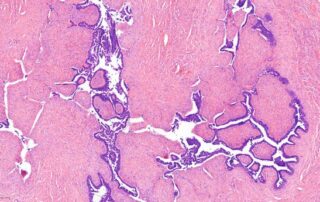

Pathologien der Mamma im juvenilen Alter

Läsionen in der juvenilen Mamma sind überwiegend benigne und gehen häufig mit der physiologischen Brustentwicklung einher. Die Sonographie stellt die diagnostische Methode der Wahl dar. Die Abgrenzung zwischen benignen und malignen Läsionen ist klinisch jedoch nicht immer möglich und Bedarf im Einzelfall, insbesondere bei rascher Größenprogredienz, Radiatio in der Vorgeschichte, bekannter BRCA-Mutation oder auffälliger Familienanamnese, einer histopathologischen Diagnosesicherung.